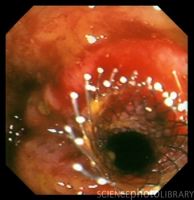

Стентирированием стенозирующих опухолей толстой кишки неотложную ситуацию (обтурационную непроходимость) можно перевести в плановую.